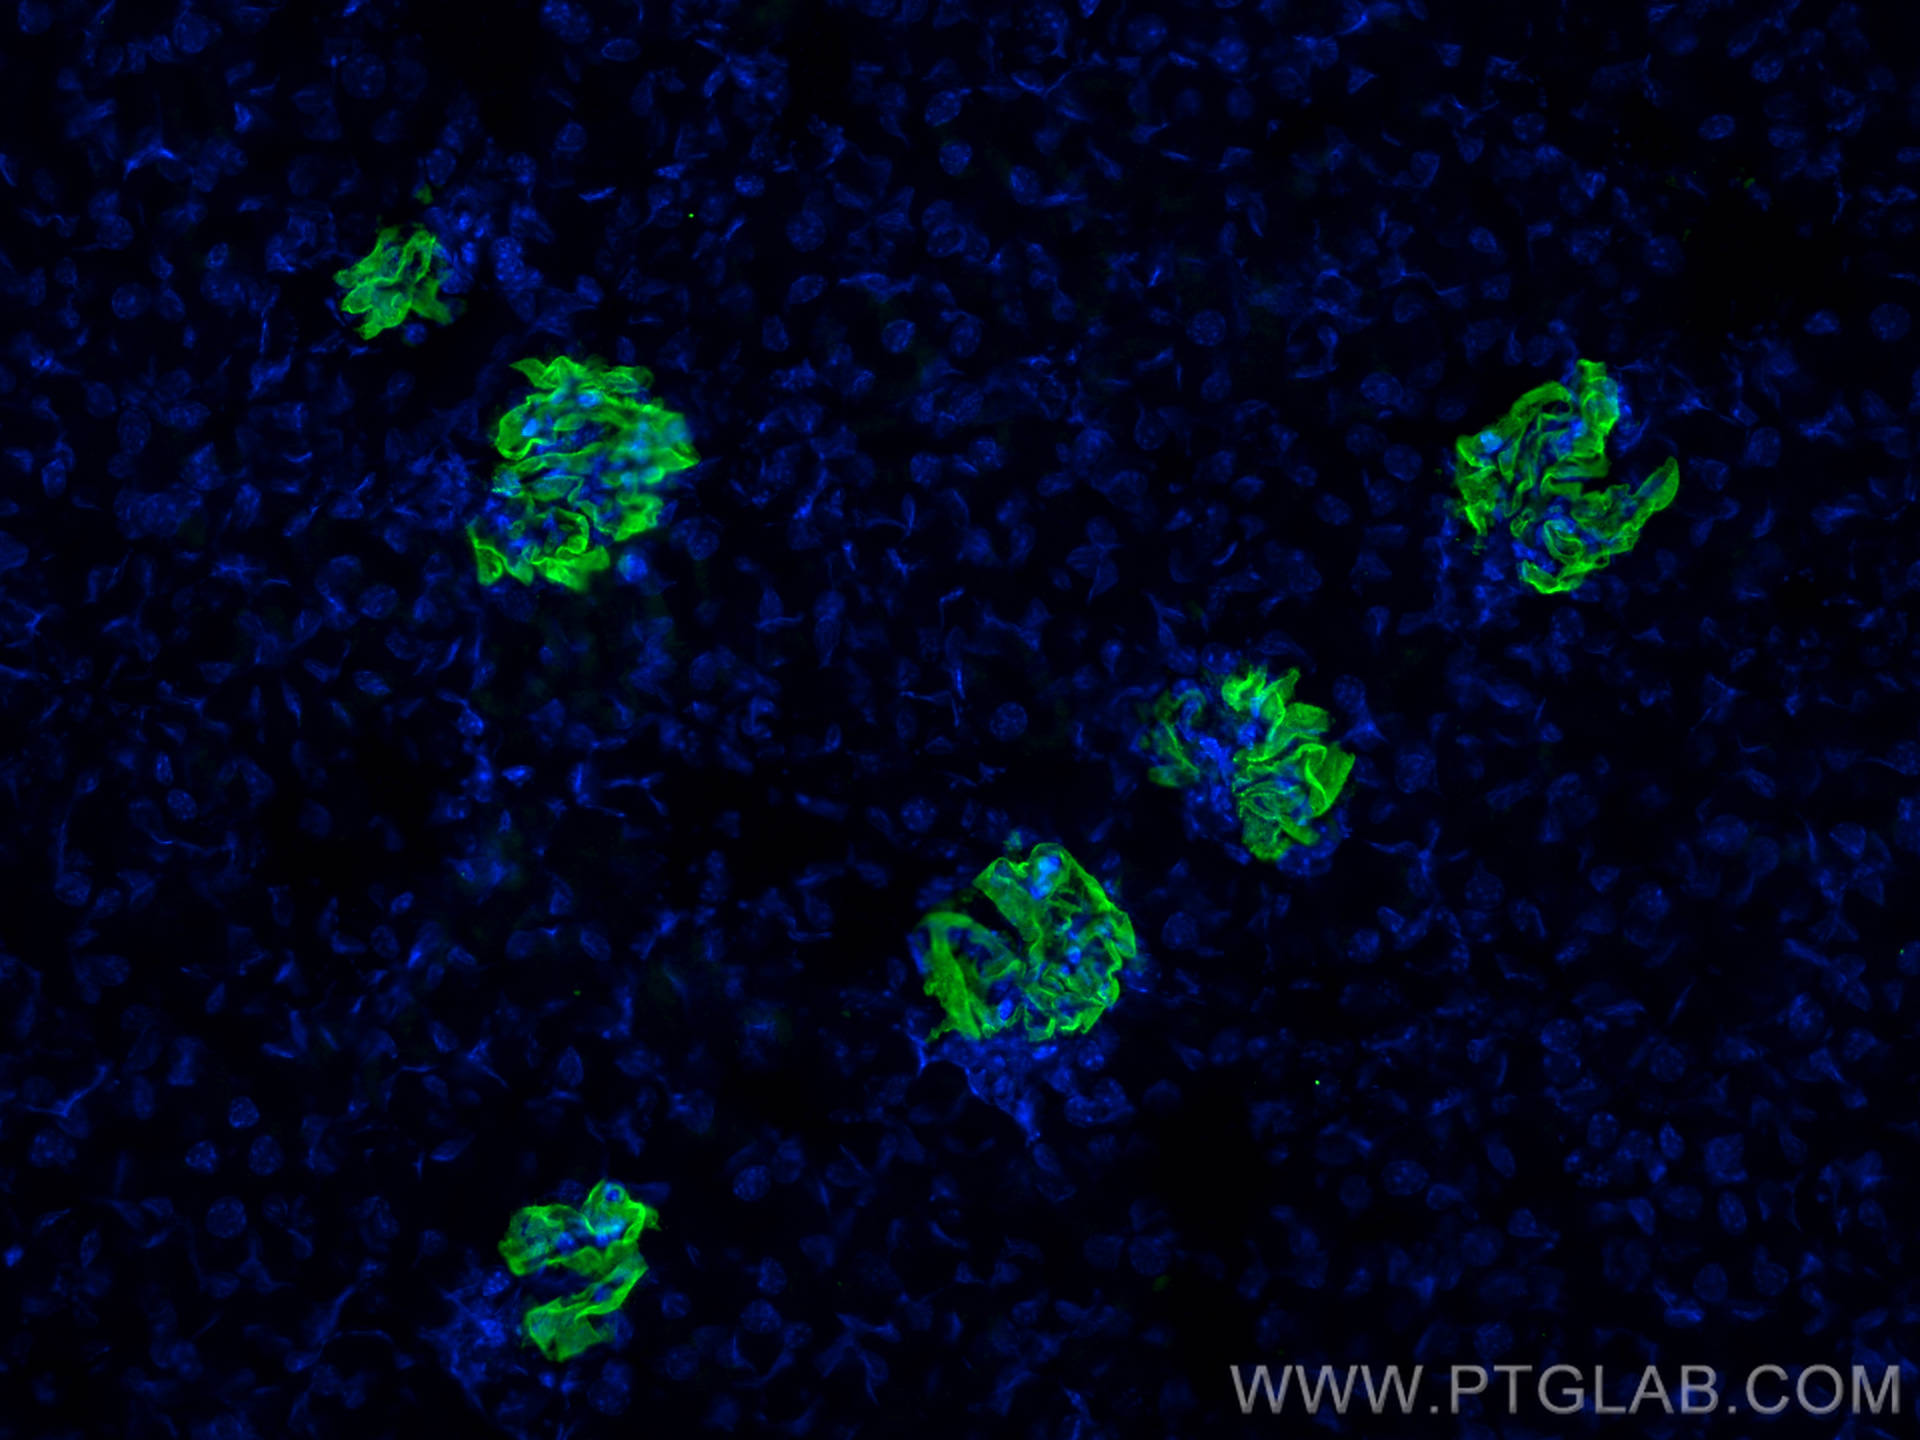

| Positive IF detected in | mouse kidney tissue, zebrafish embryos |